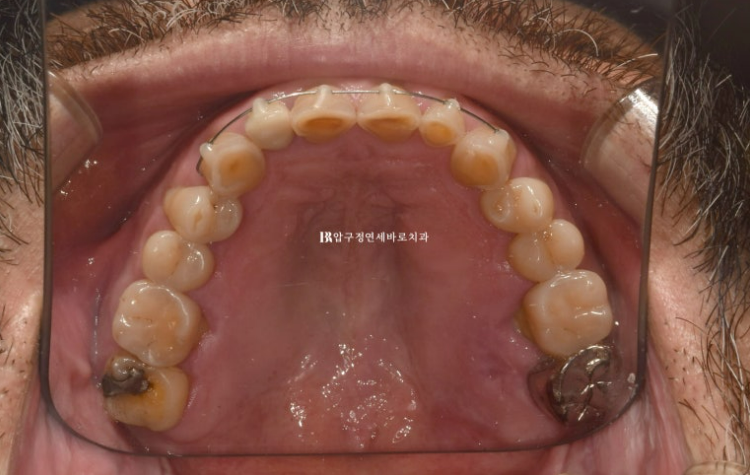

3개월에 걸쳐 앞니 교정을 간단하게 하고 6월 드디어 무삭제 라미네이트 치료를 했습니다.

24.06

무삭제 라미네이트의 실제 두께를 알 수 있는 사진입니다.

삭제를 하지 않았음에도 원래 치아보다 두꺼워짐이 거의 없죠

무삭제 라미네이트의 핵심은 바로 얇게 만드는 것 입니다.

24.03~24.06

옥니 치아가 교정과 무삭제라미네이트로 개선이 되었습니다.

미소가 훨씬 젊어보입니다.